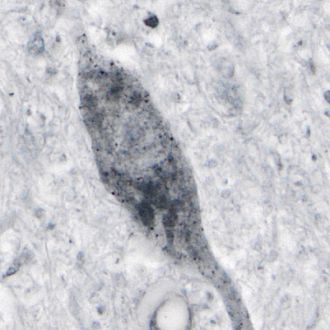

Abnormal SOD1 protein detected in human spinal cord tissue

Normally, the protein superoxide dismutase 1 (SOD1) protects cells, but a mutation in its gene is thought to make the protein ‘toxic’; this toxic protein form is associated with hereditary forms of ALS. Abnormal mutant SOD1 is only found in regions of the spinal cord where nerve cells die, implicating this abnormal protein in cell death.